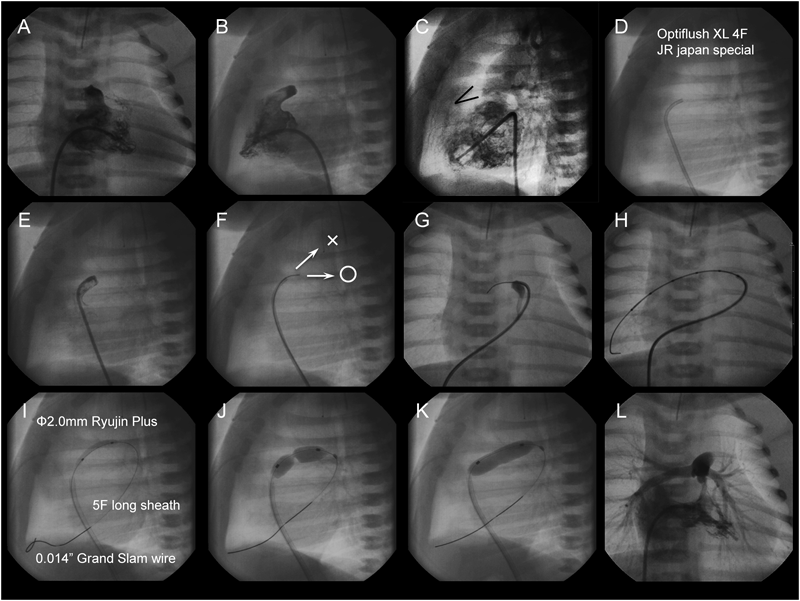

The main pulmonary arteriogram revealed the constriction of the pulmonary arterial side of the arterial duct (AD), which was not covered by the previously implanted stent (A; arrow). The guide wire was formed in vitro into an inverted U-shape to fit the curvature of the AD (B, arrows). During the procedure, blood pressure was maintained at a higher level after intravenous infusion of epinephrine (10 µg), and a stent (6 mm in diameter and 18 mm in length) (Palmaz Genesis® 1860) was delivered into the AD by bare delivery (C) and implanted (D).

2006年10月から2013年10月の間に当院で12症例(Table 5)に施行したDSの最中または後に生じた合併症・問題点をTable 6に示す.最多の問題は手技中の血圧低下であり,12症例中7症例に認められ,その内の5症例はHLHSであった.特に大動脈弁閉鎖では血圧低下から冠血流が低下して重篤な心機能低下をきたし得るので,Bare stent deliveryやエピネフリン静注などの対応を施して手技に臨む必要がある.